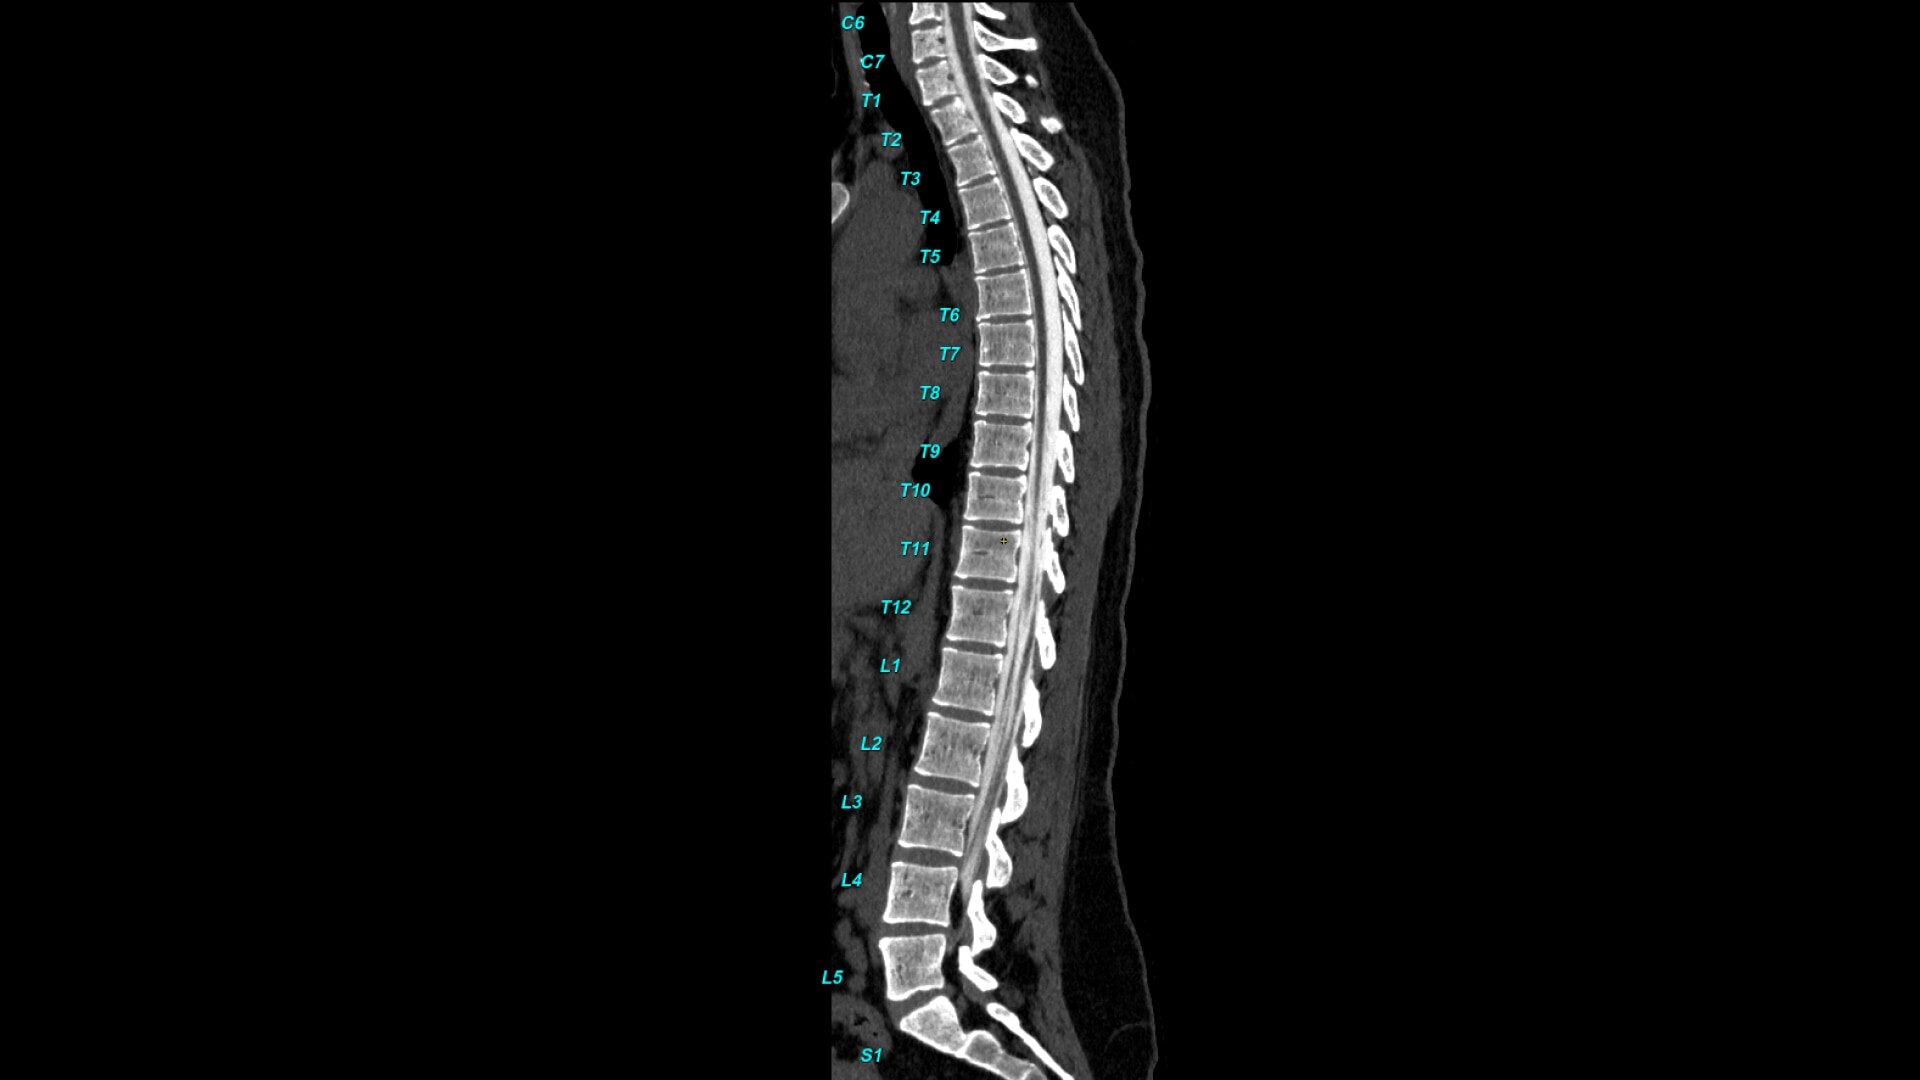

Bone VCAR

Spine assessment with deep-learning based CT application.

Automated spine identification and labelling.

>90% labeling accuracy based on Deep learning algorithm trained on global datasets acquired with a broad range of acquisition parameters.

• Automated spine labeling

• Automated generation of a 3D trace to generate oblique and straightened reformat views

• Accessible for any exam type: trauma, oncology, dedicated spine, general imaging

• Works on full spine acquisitions as well as limited acquisitions containing segments of the spine